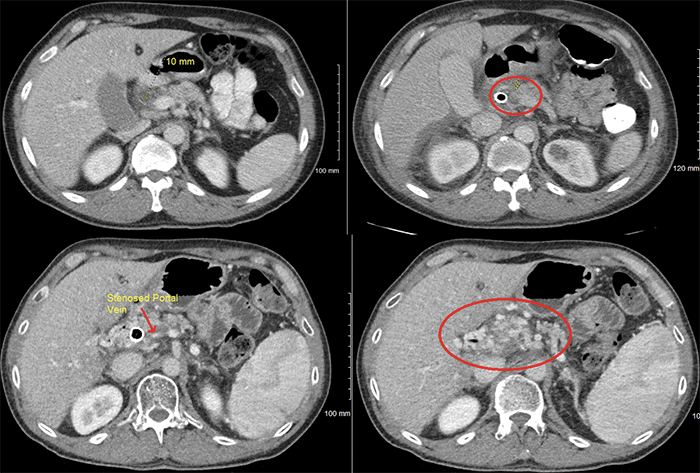

This patient is a 47-year-old male who presented to urgent care with intermittent abdominal pain and jaundice for almost one month. Subsequent workup revealed elevated liver function tests with a total bilirubin of 17.8 and a CA 19-9 of 44. An initial CT scan of the abdomen/pelvis revealed a pancreatic mass in the uncinate process (Figure 1A). The patient underwent ERCP with stent placement and EUS with biopsy that would prove to be adenocarcinoma. Days later, the patient developed acute pancreatitis with a new PV thrombosis (Figure 1B). He was placed on Lovenox and subsequently underwent neoadjuvant therapy with modified FOLFIRINOX followed by chemoradiation for margin augmentation. Upon surveillance during his neoadjuvant treatment, he was found to have occlusion of the PV (Figure 1C) and cavernous transformation, which is the formation of periportal or intrahepatic venous collaterals (Figure 1D).7

Figure 1. CT Scans at Various Points in Treatment. Published with Permission

Clockwise: A) CT initial diagnosis showing mass; B) CT showing PV thrombosis; C) CT showing PV stenosis; D) CT peripancreatic varices